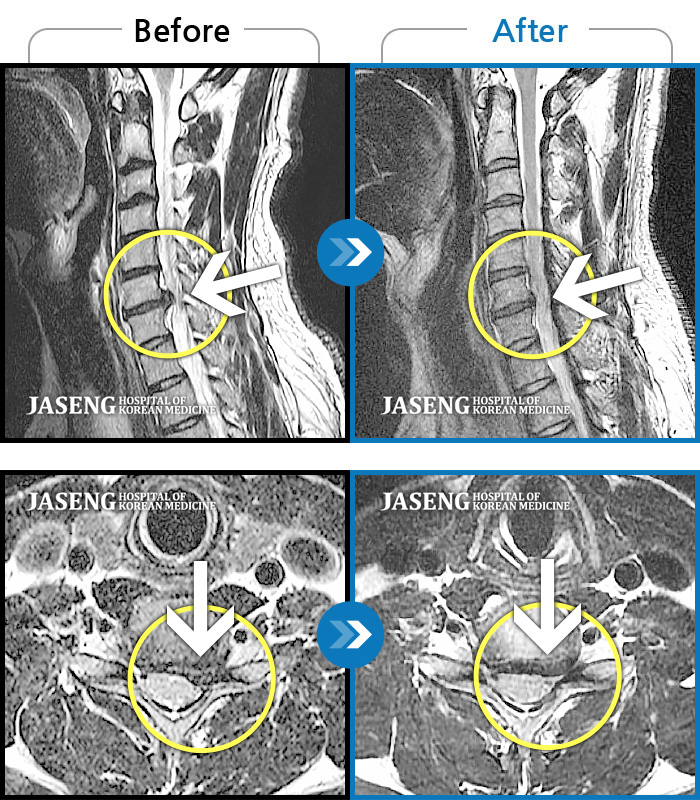

목디스크

강남 · 강만호 원장

양측 승모근 통증과 목 통증, 견갑골 통증으로 고개를 돌릴때 통증을 호소하는 환자였습니다.

촬영시기

2019.11.18 ~ 2024.07.30

2024.08.09

조회수 478